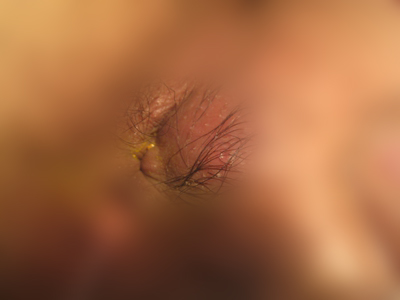

肛门脓肿症状图片

肛门脓肿常位于肛门后方或侧方皮下间隙,因此又称肛周皮下间隙脓肿。脓肿范围一般不大。主要症状为肛周持续性跳动性疼痛,全身感染性症状不明显。病变处明显红肿,有硬结和压痛,脓肿形成可有波动感,穿刺易抽出脓液。